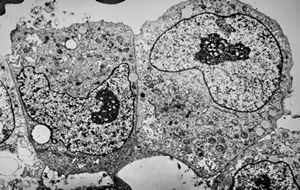

F,49y. | purulent meningitis- meningococcal v.s.